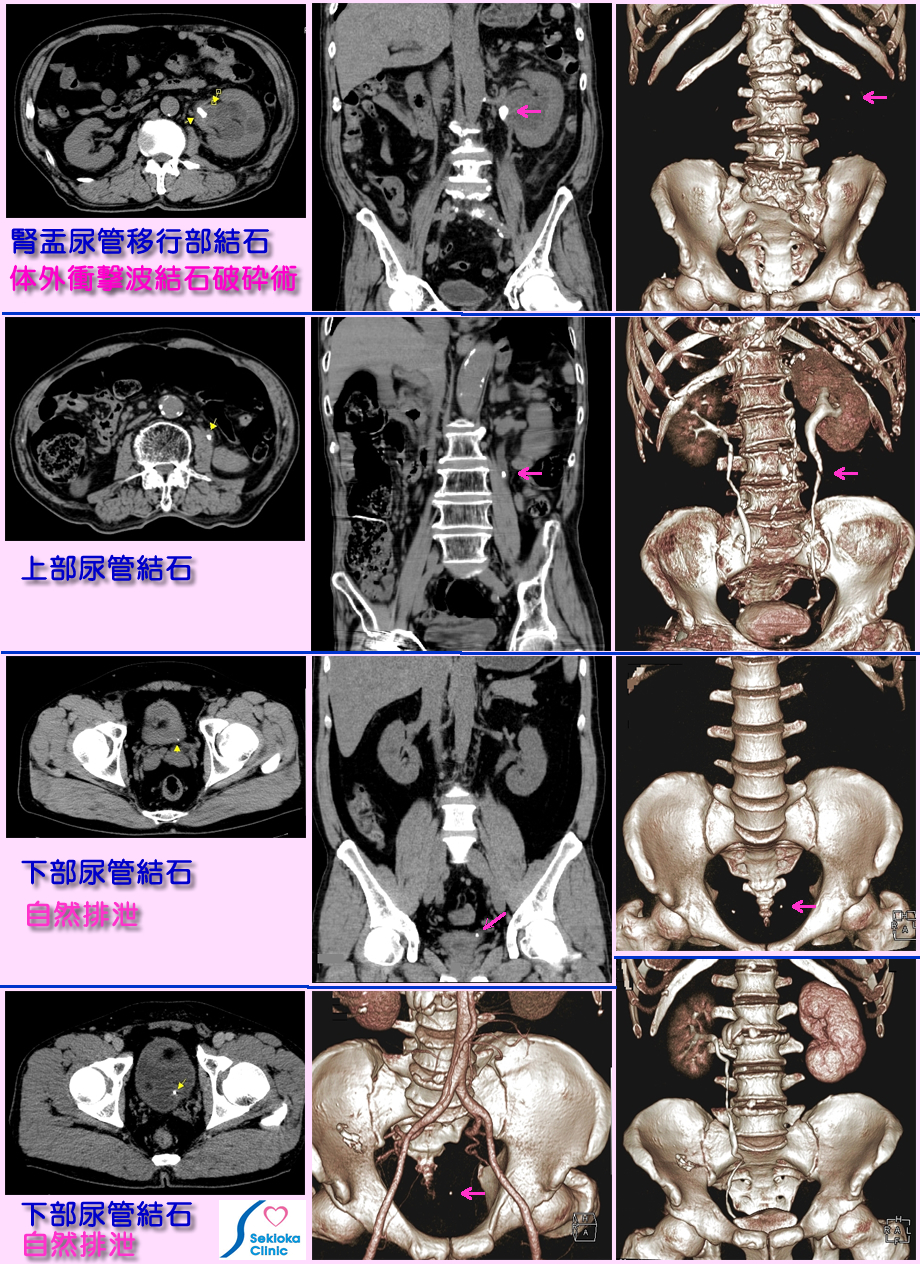

| 診断 | 尿に血液の混入で疑い、確定診断および結石の陥入部位の診断は超音波エコー、CT(小さな石の検索には連続的に薄く撮影できるMDCTがよい)。超音波エコーは腎臓から膀胱まで連続的に検索することは困難で 全体を洩れなく検索できるCTが望ましい。腎盂内、尿管内の結石を矢印で示します。下段左は結石による右尿管の急性閉塞(尿管が造影されていない)を示します。 |

| 治療 | 初期は鎮痛剤で痛みを抑える。結石が小さい場合は自然排泄を待つ。腎盂、上部尿管に存在し大きく自然排泄が期待し難い場合は 衝撃波などで石を破壊。結石の成分を調べ、原因となる血液異常(高い尿酸、Ca値など)を正常化するため、食事注意や服薬をして再発を予防します。 |